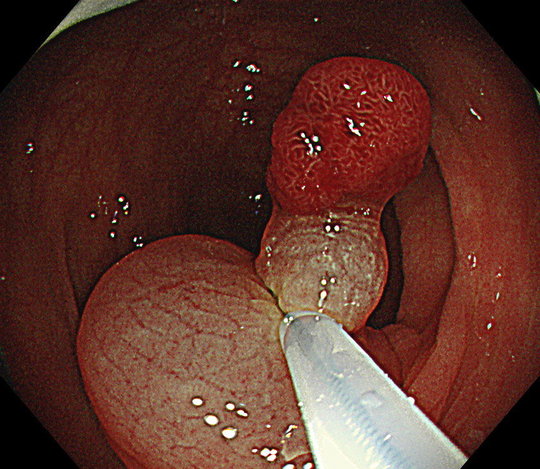

さらに桐山クリニックでは、病変発見時に、約80倍まで拡大観察することが可能な拡大内視鏡を標準使用しています。この内視鏡を使用することで、病変が腫瘍であるかどうか、切除が必要かどうか、何度も検査をすることなく、ボタン1つで評価することができます。

NBI拡大観察

病変が見つかったときには、NBI(Narrow Band Imaging:狭帯域光観察)という画像強調技術を駆使し、そのポリープが腫瘍であるかどうか、内視鏡で切除すべきか、手術などが必要かどうかなど精密検査も同時に行うことができます。

NBI診断や拡大機能を使用した内視鏡診断は高度な技術と豊富な経験が必要です。大学病院や総合病院でも十分に検査ができる医師が少ないところもありますが、当院では国立がんセンター中央病院での豊富な検査や診断経験に基づき精度の高い検査を行っています。